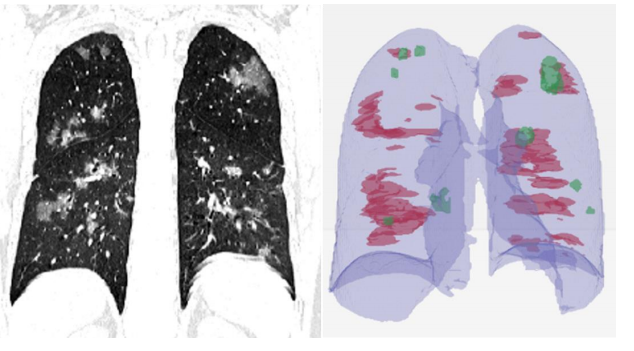

In yet another paper, titled Rapid AI Development Cycle for the Coronavirus (COVID-19) Pandemic: Initial Results for Automated Detection & Patient Monitoring using Deep Learning CT Image Analysis, the authors use a 3-D U-Net architecture to extract the lung out of the scan (same function as the VNET20 model).

Then these lung crops are classified by a neural network. The entire lung is passed to the classification network, unlike the previous work where ROIs were extracted from the lung before classification. The authors then use the Grad-CAM technique to create "heatmaps" of the lungs.

In addition to classifying 2-D lung crops, the authors also use an off-the-shelf software, RADLogics, that detects nodules and small opacities within a 3-D lung volume. Then, the patches from the software and the heatmaps from the earlier stages are combined to create a 3-D visualization.

Now let's consider the CT scan of a patient who's suffering from pneumonia brought on by COVID-19.

Generally, pneumonia causes fluid to build up in the lung, which manifests itself as opacities in the lung. The literature on application of deep learning to diagnose COVID-19 using CT scans does point to some distinct characteristic features found in lung CT scans of COVID-19 as compared to other types of pneumonia, resulting from different causes.

A paper, titled Deep Learning System to Screen Coronavirus Disease 2019 Pneumonia, lists three such characteristics:

"...ground-glass appearance, striking peripheral distribution along with the pleura, and usually more than one independent focus of infections for one case."

- The first means that the opacities in the lung look like ground-glass.

- The second means that the majority of these opacities occur along the edge of the lung.

- The third means that we can have more than one such cluster of opacities.

All three of these characteristics can be observed in the CT scan image of the lung above.